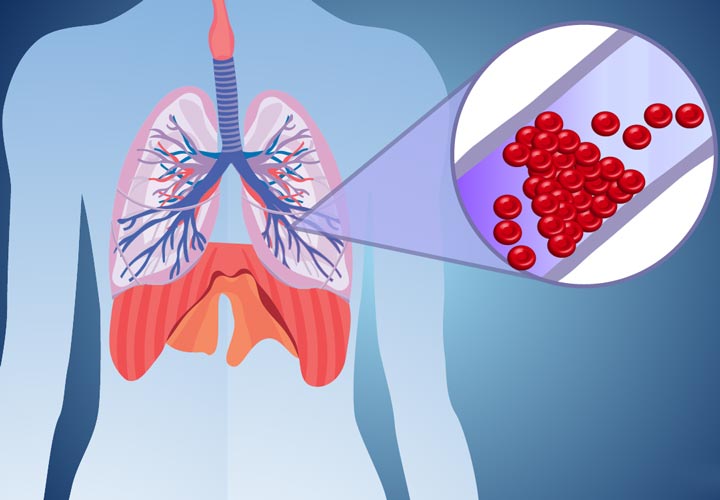

آمبولی ریه، انسداد در یکی از عروق در ریه است. آمبولی ریه در اکثر موارد توسط لختههای خونی ایجاد میشود که از پاها یا بهندرت سایر قسمتهای بدن به سمت ریهها حرکت میکنند (ترومبوز ورید عمقی).

ازآنجاکه این لختهها جریان خون به ریه ها را مسدود میکنند، آمبولی ریه میتواند بسیار خطرناک باشد. با اینحال درمان سریع، خطر مرگ را تا حد زیادی کاهش میدهد. انجام اقدامات لازم برای پیشگیری از ایجاد لختههای خون در پاها به محافظت از شما در برابر آمبولی ریه کمک خواهد کرد.

آمبولی ریه زمانی اتفاق میافتد که یک توده از مواد – اغلب یک لختهی خون – داخل یک شریان گیر میکند. این لختههای خون اغلب از وریدهای عمقی پاها میآیند. این عارضه به ترومبوز ورید عمقی (DVT) معروف است.

در بسیاری از موارد، لختههای متعدد در آمبولی ریه دخیل هستند. بخشهایی از ریه که توسط شریانهای مسدودشده اداره میشدند، از خون تُهی میشوند و ممکن است ازبین بروند (مرگ بافت ریه). این وضعیت انفارکتوس ریوی نامیده میشود و باعث میشود که رساندن اکسیژن به سایر قسمتهای بدن برای ریهها دشوار شود.